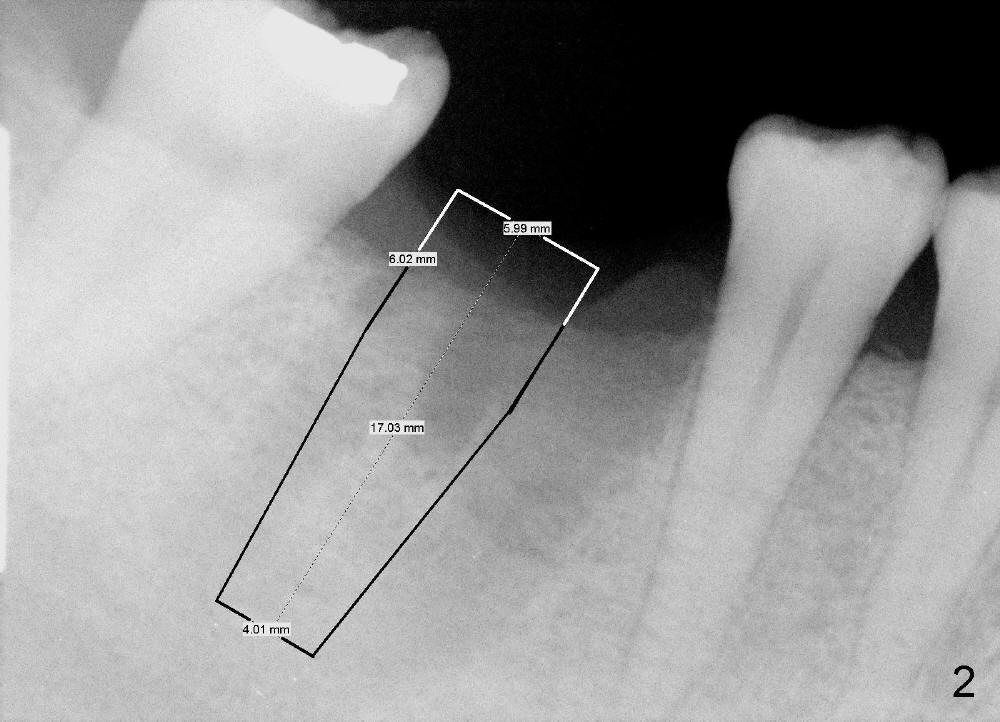

A 43-year-old lady had the lower right first molar extracted in other office last month. The socket appears to be healing normally (Fig.1). Tatum tapered implant 6x17 mm is planned (Fig.2). The implant is to be placed inside the septum (Fig.3 red outline; black: mesial and distal sockets; yellow: the upper border of the inferior alveolar canal). Either 1.5 mm pilot drill or 2 mm RT is used to start osteotomy in the septum at the depth of 17 mm (Fig.4 white outline). The osteotomy is enlarged with alternating use of osteotomes and 17 mm series tapered drills or Bicon reamers if autogenous bone will be needed (Fig.5 black), while the septal bone is pushed mesiodistally (arrows). After application of taps, an appropriately sized implant is placed (Fig.6 white). The septal bone continues expanding (arrows), whereas the mesial and distal sockets are being decreased.